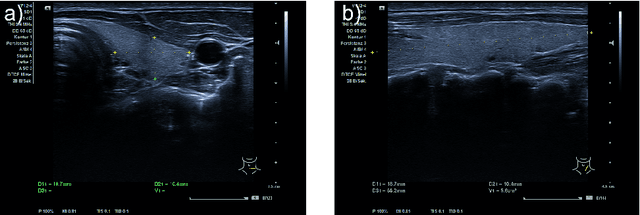

Abstract:In nuclear medicine, radioiodine therapy is prescribed to treat diseases like hyperthyroidism. The calculation of the prescribed dose depends, amongst other factors, on the thyroid volume. This is currently estimated using conventional 2D ultrasound imaging. However, this modality is inherently user-dependant, resulting in high variability in volume estimations. To increase reproducibility and consistency, we uniquely combine a neural network-based segmentation with an automatic robotic ultrasound scanning for thyroid volumetry. The robotic acquisition is achieved by using a 6 DOF robotic arm with an attached ultrasound probe. Its movement is based on an online segmentation of each thyroid lobe and the appearance of the US image. During post-processing, the US images are segmented to obtain a volume estimation. In an ablation study, we demonstrated the superiority of the motion guidance algorithms for the robot arm movement compared to a naive linear motion, executed by the robot in terms of volumetric accuracy. In a user study on a phantom, we compared conventional 2D ultrasound measurements with our robotic system. The mean volume measurement error of ultrasound expert users could be significantly decreased from 20.85+/-16.10% to only 8.23+/-3.10% compared to the ground truth. This tendency was observed even more in non-expert users where the mean error improvement with the robotic system was measured to be as high as $85\%$ which clearly shows the advantages of the robotic support.

Abstract:Background: Thyroid volumetry is crucial in diagnosis, treatment and monitoring of thyroid diseases. However, conventional thyroid volumetry with 2D ultrasound is highly operator-dependent. This study compares 2D ultrasound and tracked 3D ultrasound with an automatic thyroid segmentation based on a deep neural network regarding inter- and intraobserver variability, time and accuracy. Volume reference was MRI. Methods: 28 healthy volunteers were scanned with 2D and 3D ultrasound as well as by MRI. Three physicians (MD 1, 2, 3) with different levels of experience (6, 4 and 1 a) performed three 2D ultrasound and three tracked 3D ultrasound scans on each volunteer. In the 2D scans the thyroid lobe volumes were calculated with the ellipsoid formula. A convolutional deep neural network (CNN) segmented the 3D thyroid lobes automatically. On MRI (T1 VIBE sequence) the thyroid was manually segmented by an experienced medical doctor. Results: The CNN was trained to obtain a dice score of 0.94. The interobserver variability comparing two MDs showed mean differences for 2D and 3D respectively of 0.58 ml to 0.52 ml (MD1 vs. 2), -1.33 ml to -0.17 ml (MD1 vs. 3) and -1.89 ml to -0.70 ml (MD2 vs. 3). Paired samples t-tests showed significant differences in two comparisons for 2D and none for 3D. Intraobsever variability was similar for 2D and 3D ultrasound. Comparison of ultrasound volumes and MRI volumes by paired samples t-tests showed a significant difference for the 2D volumetry of all MDs, and no significant difference for 3D ultrasound. Acquisition time was significantly shorter for 3D ultrasound. Conclusion: Tracked 3D ultrasound combined with a CNN segmentation significantly reduces interobserver variability in thyroid volumetry and increases the accuracy of the measurements with shorter acquisition times.